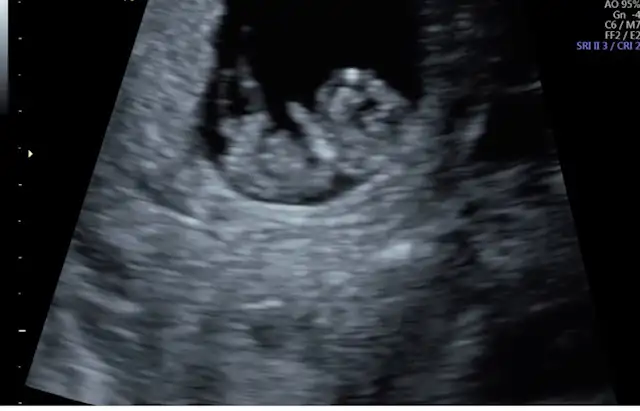

Merhaba kızlar çok şükür evlatlarımız büyüyor ve sağlıklılar rabbim isteyen herkese nasip etsin. Artık korkularımı bırakıyorum. Rabbim kötülüklerden korusun hepimiz yavrularımızı kucağımıza almayı nasip etsin. Ultrasona göre 3 gün önden gidiyor dedi bir sorun yoktur umarım. Ve bize muaynede kolunu oynatırken denk geldi çok farklı bi duyguydu. Rabbime şükürler olsun. 3 hafta sonra tekrar çağırdı sağlık ocağında yapılması gereken testleri istedi dr. 2 tane olan testi karşılamıyor sağlık ocağı rubella ve toxoplazma bunlar çok önemlimi dikkat etmek gerekli bir bilgi varmı. Birde sağlık ocağı hamilelik takibi yapılacak dendi mayıs ayı gibi tetenoz aşısı varmış yqpılması zorunlumu. Cinsiyet ne zaman net öğreniriz.